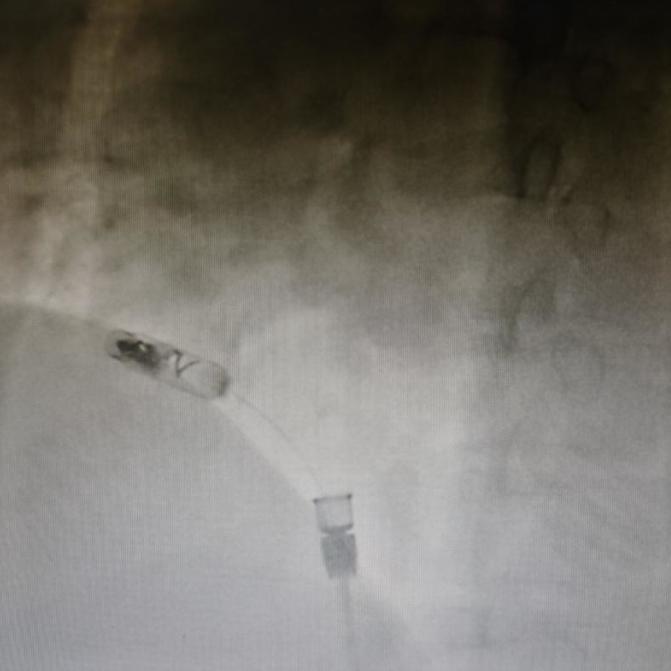

猪尾右前斜造影

起搏器旋入

进入对接栓模式并进行张力测试

起搏器释放